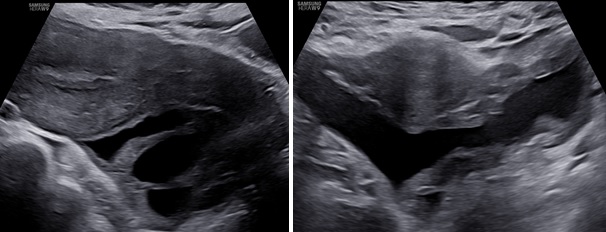

– Siêu âm: Tử cung và buồng trứng (T) bình thường, buồng trứng (P) không quan sát thấy. Từ cùng đồ sau lan qua hố chậu (P) có 1 khối echo hỗn hợp không đồng nhất, kích thước# 105x 98x 59 mm, bên trong có nhiều mảng echo dày bờ không đều, di động khi di chuyển đầu dò, có tăng sinh mạch máu mức độ 3 Ở ngoại vi khối này có hình ảnh mô buồng trứng bình thường. Dịch cùng đồ# 8 mm.

– Chẩn đoán siêu âm: Theo dõi khối huyết tụ thành nang (HTTN) chưa loại trừ khả năng: u đơn thùy buồng trứng (P) có mảng xuất huyết bên trong.

Hình 1: Mặt cắt ngang qua bụng trên thang xám và Doppler, khối u nằm sau tử cung lệch qua hố chậu phải có khối phản âm hỗn hợp không đồng nhất, có tăng sinh mạch máu ngoại vi

Hình 2: Mặt cắt dọc và ngang qua ngã âm đạo thấy khối u có phản âm hỗn hợp, bên trong có nhiều mảng phản âm dày, di động khi di chuyển đầu dò, giúp hướng đến bản chất xuất huyết.